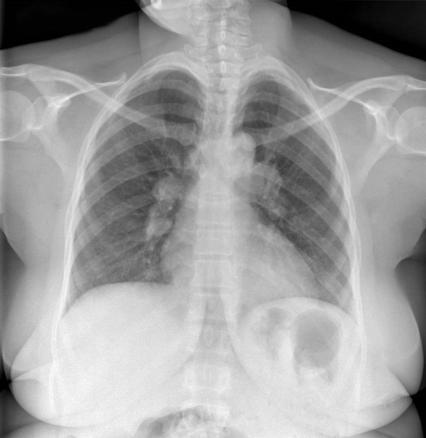

Forme de sarcoïdose qui se manifeste par une triade associant : un érythème noueux, une arthrite et, comme sur cette radiographie, des adénopathies médiastinales.